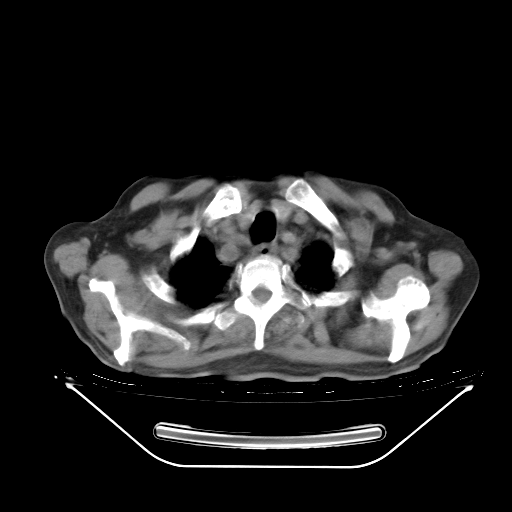

今天复查肺部CT,发现双肺广泛磨玻璃样改变。所以我把3月19日和5月9日相隔50天的肺部CT上传。请大家会诊。

5月9日肺部CT(在4月27日齐鲁医院肺部CT描述部分肺组织磨玻璃样改变,12天后肺组织广泛磨玻璃样改变)

大致读了系列胸部CT:纵隔窗无明显异常,肺窗:从4、27至今:主要是双肺中下野外带可见毛玻璃样改变,目前处于急性肺泡炎阶段,至于原因考虑1、结替组织或胶原血管性疾病所致?2、恶性疾病如恶组在肺部所致的表现或细支气管肺泡癌?3、药物或其它原因如肺蛋白沉着症所致肺泡炎目前不太可能?总之,明天就去请我院的呼吸科、感染科、血液科和临免专家会诊哈。